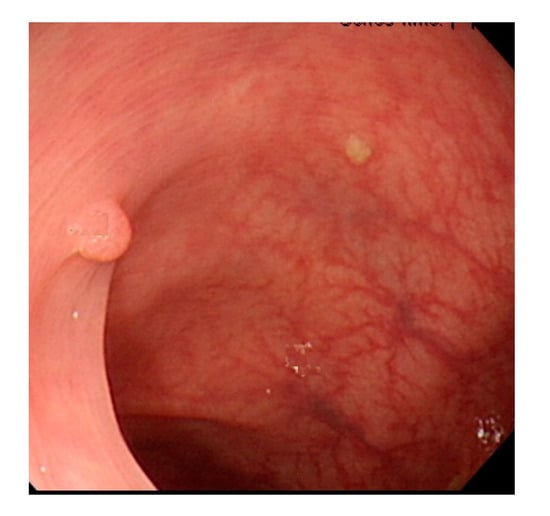

In polyp classification, neoplastic polyps were likely to be misjudged as hyperplastic polyps when polyp textures were not obvious (Figure 16), images had an excessively low resolution, or when polyps were smaller than 1800 pixels (Figure 17). Hyperplastic polyps, however, were likely to be misjudged as neoplastic polyps because of the WL around polyps in the images and when polyps were smaller than 1800 pixels.

Figure 16.

Unobvious polyp textures.

Figure 17.

Polyp image size below 1800 pixels.